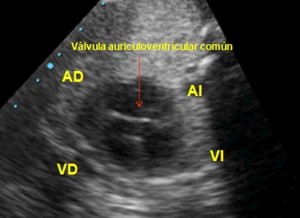

Canal av completo:

(ver figura y video del canal haciendo clic aquí). Se observa la casi ausencia de los tabiques interauricular e interventricular (no existe línea blanca que separe completamente la AD de la AI y el VD del VI). Además, en lugar de existir una válvula mitral y una tricúspide independientes, solo aparece una línea central en color blanco que es una válvula (auriculoventricular común) cubriendo ambos anillos. La asociación de estos defectos se conoce con el nombre de canal auriculoventricular común (o defecto del septo auriculoventricular).

Cuatro Cámaras, Canal av